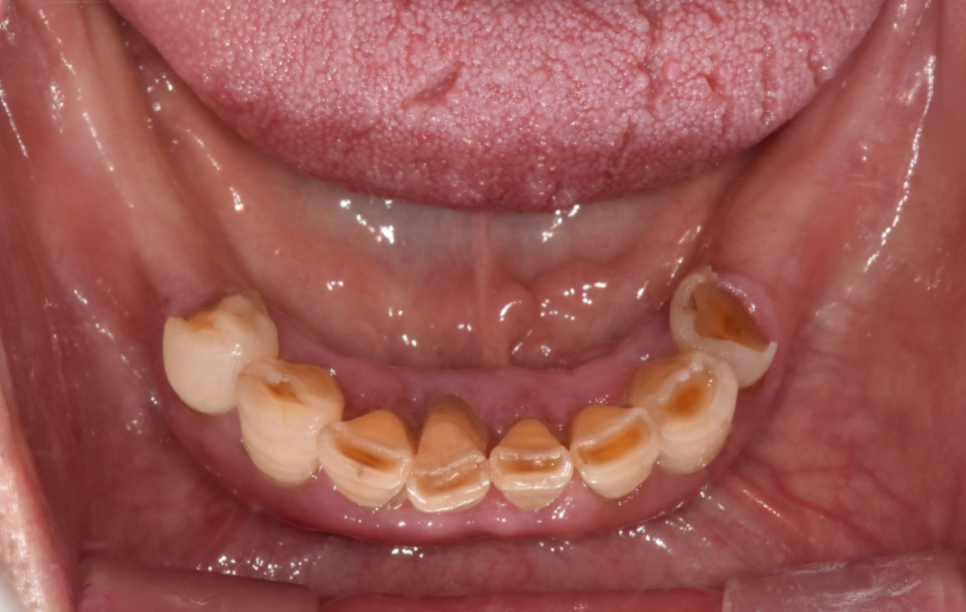

다수의 치아 상실

23.08.17

그동안 식사를 어떻게 하셨는지

잘 모르겠을 정도로

치아가 많이 상실된 상태였습니다.